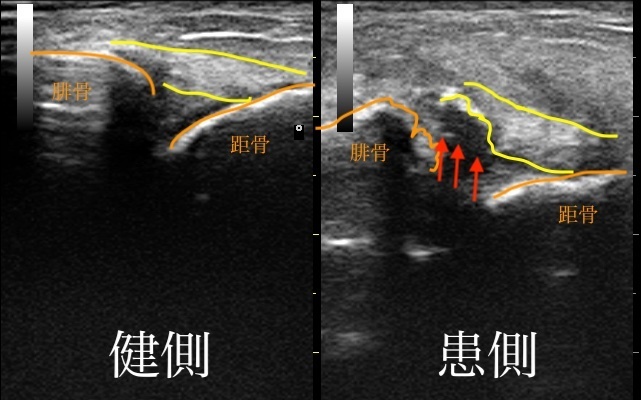

エコーでも詳細に確認します

当院では、エコー画像も観察し、小さな骨折でも見逃しのないよう詳細に確認しております。

今回は、外観上も大きな腫れがありますが腫れが小さくても骨折の場合も多々あります。

的確な判断をしないと後遺症のリスクも上がってしまいますので注意が必要です。